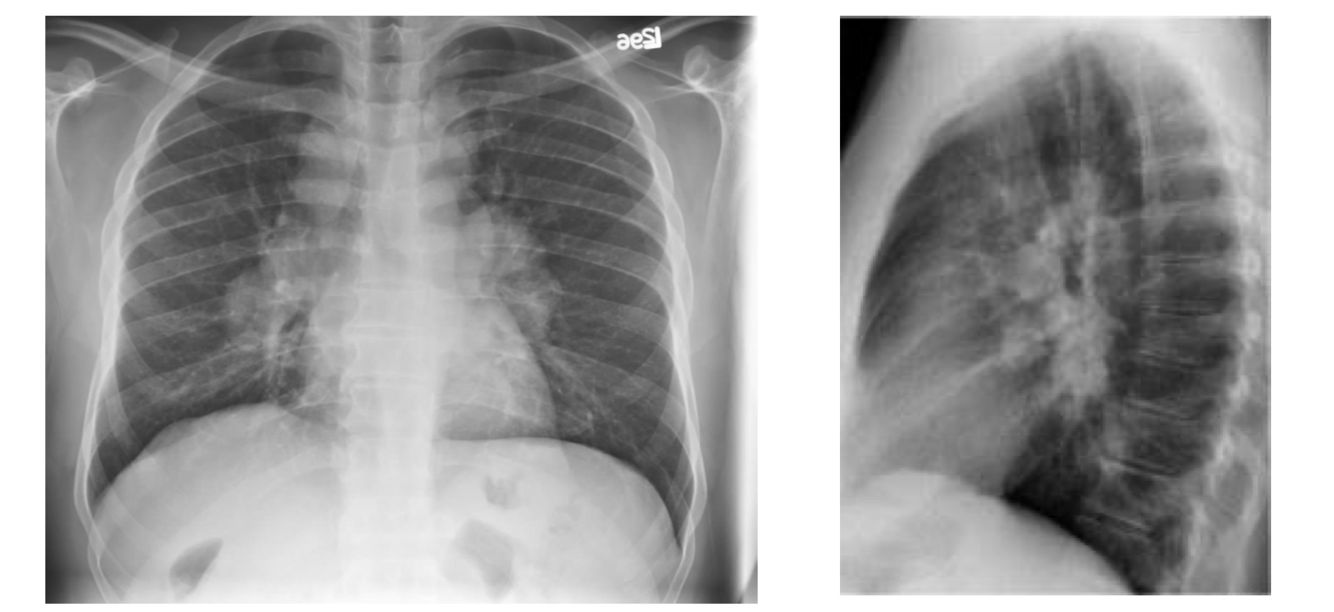

75M with progressive dyspnea/cough for 6 months

• Hypertension, 20pack-yr ex-smoker

• No history of CTD/malignancies/cardiac disease

• Retired librarian

• Meds: HCTZ. No allergies

Vitals normal • No H&N adenopathy • Resp exam: bibasilar crackles • Normal CV exam, clubbing on fingers.

• No signs hypervolemia

• Hgb 190 (N Indices), Platelets 185, WBC 8.0 (N Diff)

• Electrolytes/Renal Function

• Na 135, K 4.0, Cl 95, HCO3 25, Creatinine 70 (eGFR 75) • Calcium 2.35

• Liver Function Tests

• ALT 25, Bili 12, Albumin 40

thick fibrosis on the periphery of the lung.

distribution of honeycomb lung for UIP